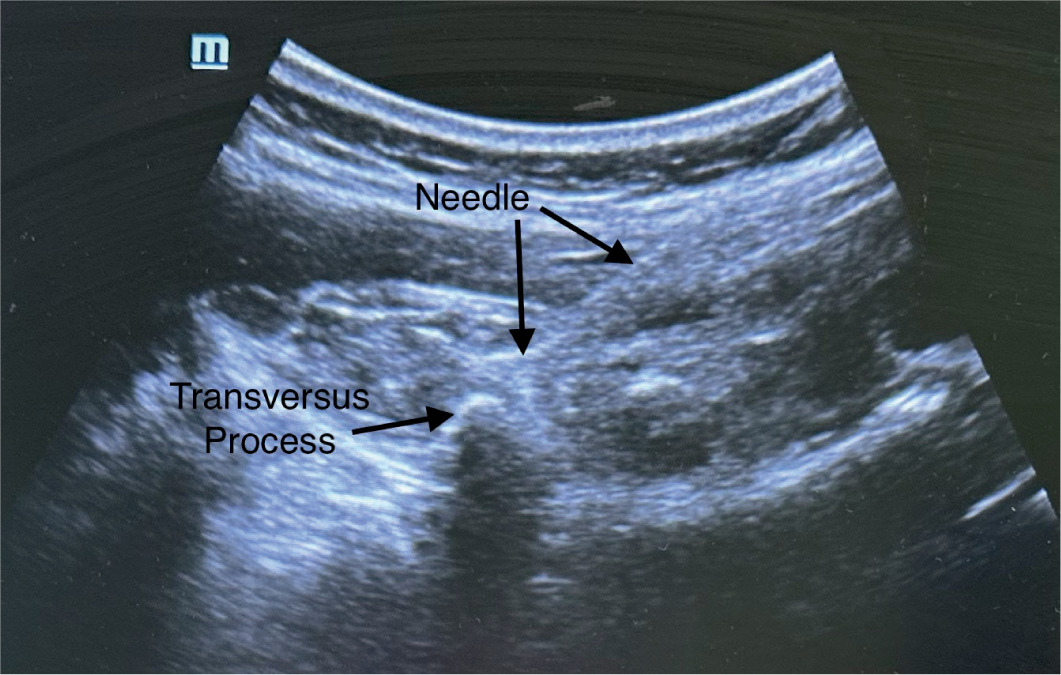

Lumbar erector spinae plane block procedure (Figure 3)

After the spinal anesthesia and before the surgical incision, the erector spinae plane block (ESPB) was performed at the L2 vertebral level. The patient was placed in the lateral position with the operated side up. We used a linear, high-frequency 4–8 Hz probe and a 22-gauge needle (Stimuplex Ultra 360, 50 mm). The transducer was placed in a paramedian sagittal orientation at the level of spinous processes. The needle was inserted in-plane from a cranial to caudal direction until the tip contacted the transverse process. We injected 0.5 mL of 0.9% isotonic saline to confirm the proper injection plane by visualizing the spread deep to the erector spinae muscles and superficial to the transverse process. After the negative aspiration, 0.5 mL kg–1 of 0.2% ropivacaine was placed to ensure the fascial plane between the transverse process and the erector spinae muscle.